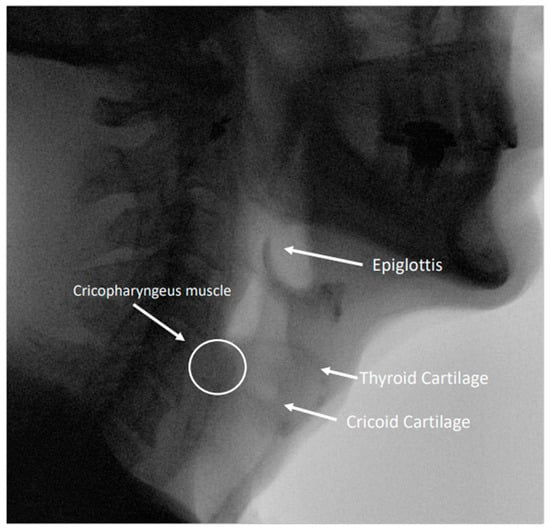

2.1. The Upper Esophageal Sphincter